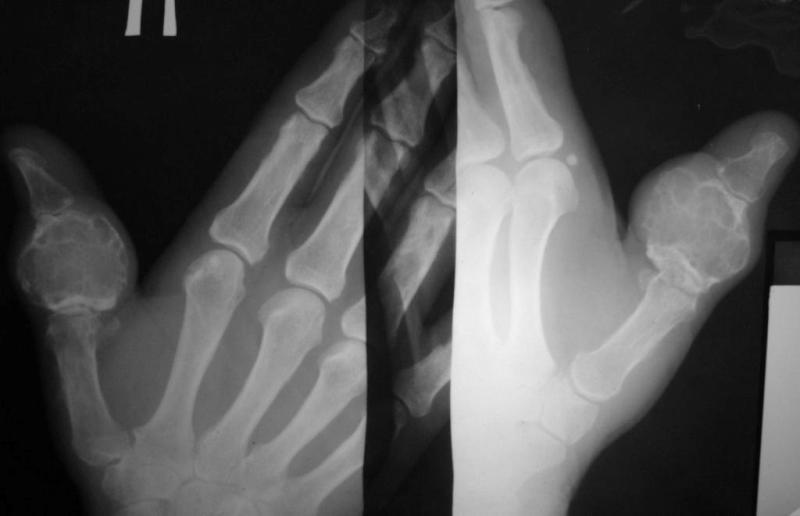

Больная, 68 лет. 10 лет назад со слов больной была травма пальца, за помощью не обращалась, была небольшая припухлость. За последние 2 года отметила рост опухолеподобного образования, появились боли, ограничение движений 1 пальца. При пальпации умеренная болезненость. Наблюдалась в поликлинике по месту жительства с диагнозами - солитарная костная киста, энхондрома.Госпитализирована с диагнозом остеобластокластома проксимальной фаланги 1 пальца правой кисти. Предлагается удаление проксимальной фаланги и костная пластика:1. трансплантатом из гребня подвздошной кости2. трансплантатом из большеберцовой кости3. трансплантатом из головки плюсневой костиУ кого есть какие-то взгляды на лечение даной больной. Спасибо за ответы.

Судя по представленным фотографиям опухолевое образование имеет выраженный мягкотканный компонент, выходит за пределы кортикала фаланги, которая мне видится разрушенной. Даже если это и остеобластокластома (гигантоклеточная опухоль), точно на этот вопрос может ответить лишь морфолог, пластика чем-либо мне видится неадекватным вмешательством, будет рецидив, а рецидивная GCT всегда более "злая", нежели первичная. Я б уже, при такой картине, выполнил бы полный стандарт обследования для больных с впервые выявленной опухолью. Тактика лечения мне видится такой - экзартикуляция на уровне пястно-фалангового сустава, после заключения морфолога - думать далее.

Чрезвычайно похоже на ОБК (красивые "мыльные пузыри")и никак не похоже на энхондрому. Насчет тщательного обследования и обязательной морфологии нет никаких возражений, учитывая возраст больной, наличие очагов просветления и в головке пястной кости, вроде бы и периостальная реакция на пястной кости. Прорыва компактного слоя не видно, что уже хорошо. Если бы это была пястная кость, то в качестве трансплантата можно было бы еще вспомнить и о малоберцовой кости.

Гигантоклеточная опухоль в возрасте 68 лет маловероятна. Сейчас морфологу необходимо изучить материал из разных участков опухоли (высока вероятность озлокачествления). Если диагноз вторичной хондросаркомы подтвердится- тщательное дообследование и наблюдение.

Имеем заключение гистологии - Хондрома